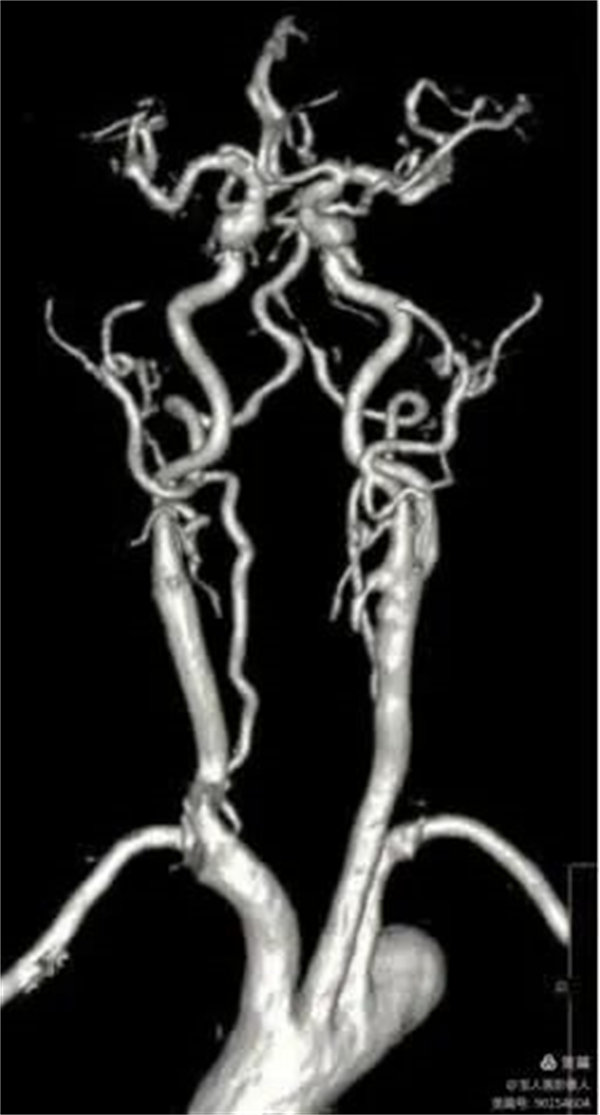

01、头颈部血管增强磁共振成像(CE-MRA)和血管壁成像(HR-VWI)

患者行CE-MRA、HR-VWI检查能清晰显示头颈部血管腔、血管壁及脑实质,完美显示动脉瘤和评估动脉瘤稳定性。

CE-MRA显示颈部血管清晰

CE-MRA主要优势:

1.血管腔的显示比MRA技术更可靠;

2.出现血管狭窄的假象明显减少,狭窄的程度反映比较真实;

3.注射对比剂后血管可显示至4-5级,且血管信号明显增强;

4.一次注射对比剂可完成多部位动脉的显示;

5.动脉瘤不易遗漏;

6.成像速度快。